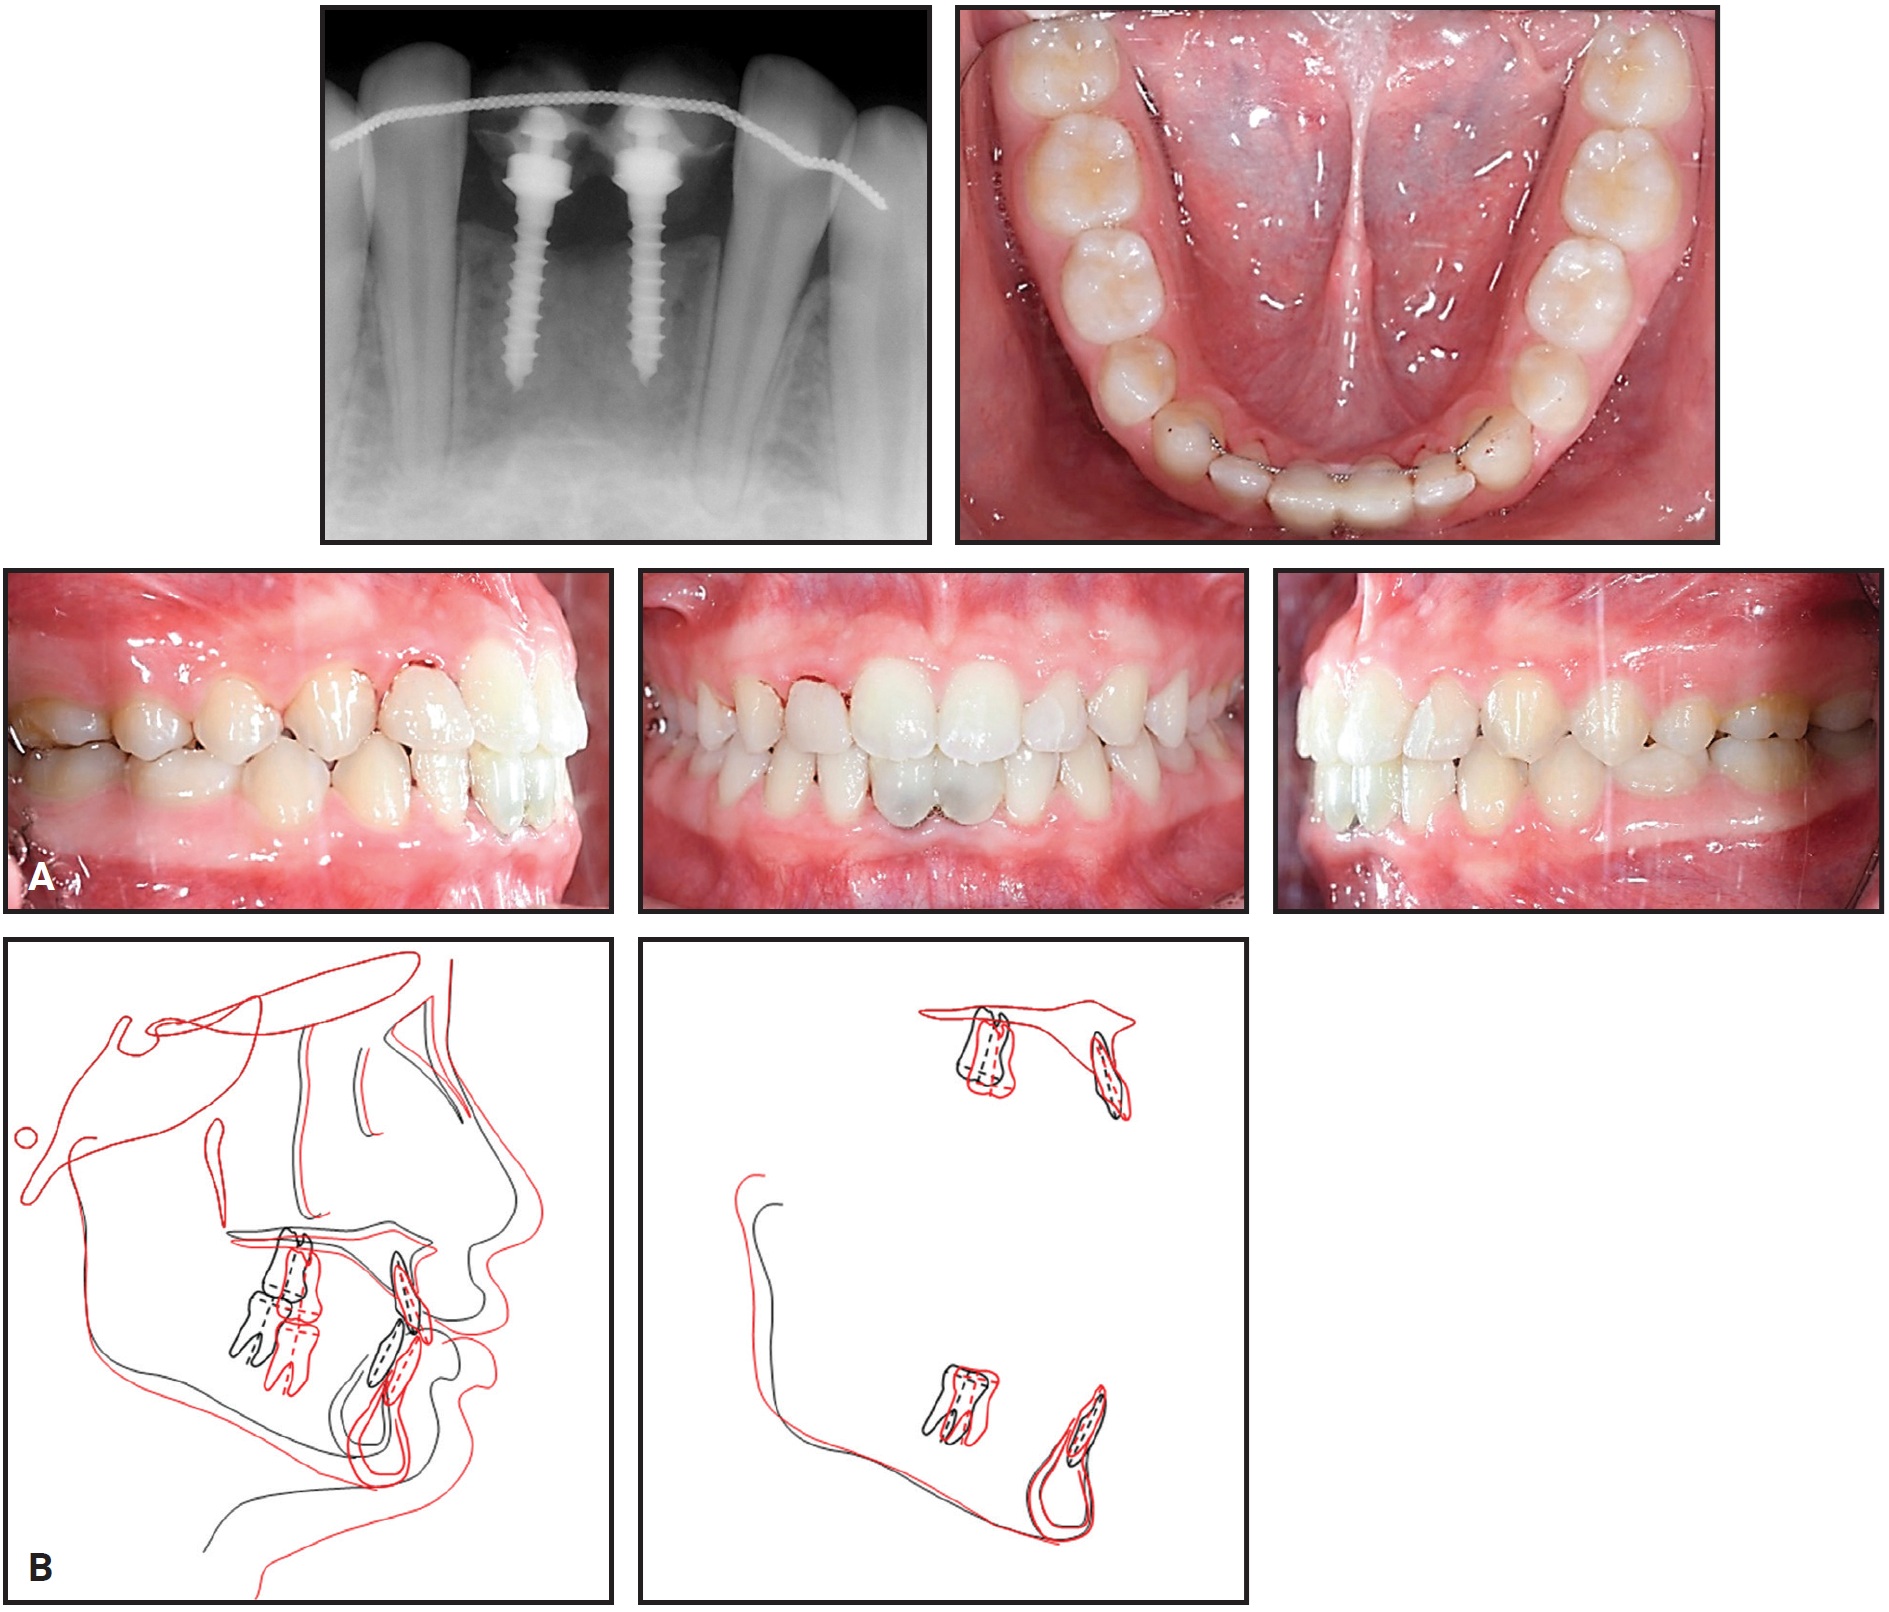

The stability of the MC-implants was confirmed radiographically after insertion (Fig. 7).

Fig. 7 MC-implants at center of alveolar bone housing, parallel to adjacent lateral incisors.

One year later, the patient exhibited a stable occlusion with Class I canine and molar relationships and favorable jaw growth (Fig. 10).

Fig. 10 A. Patient one year after treatment. B. Superimposition of pretreatment and seven-months-post-treatment cephalometric tracings.

Because of the severe external resorption of the deciduous lower central incisors, we prescribed provisional implant restorations using 1.6mm × 8mm MC-implants.2,11 Instead of a flap operation, considering the loss of anterior alveolar bone, we planned for immediate insertion of the MC-implants following extraction of the deciduous incisors. After infiltration of anesthesia, each deciduous incisor was extracted with forceps, and an MC-implant was inserted in the extraction socket at an angle following the long axis of the extracted tooth (Fig. 6).

Fig. 6 After 26 months of treatment, 1.6mm × 8mm MC-implants inserted as provisional dental implants. A. Resorbed and shortened root observed after extraction of deciduous lower right central incisor. B. MC-implants placed in extraction sockets, following original long axes of teeth. C. MC-implants in position.